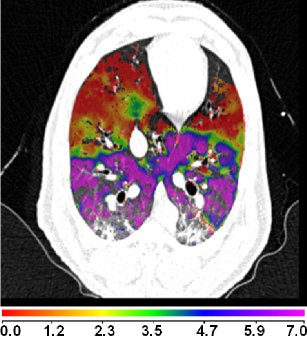

Figure 8(a) shows a comparison between the registration-derived indices of ventilation and the Xe-CT estimated sV in cube-shaped regions of interest for animal D. The corresponding Xe-CT regions in the are divided into about 100 cubes. Figure 8(b) is the Xe-CT estimate of sV. Figure 8(c), (d), (e) are the corresponding registration ventilation measures SAJ, SACJ and SAI. The regions with edema are excluded from the comparison. Figure 8(b) to (d) all show noticeable similar gradient in the ventral-dorsal direction. Notice that the color scales are different in each map and are set based on the range of values from the appropriate plot in Fig. 9.

Figure 9 shows scatter plots comparing the registration ventilation measures and the Xe-CT ventilation sV in all four animals. The SACJ column shows the strongest correlation with the sV (average ). The SAJ, which is directly related to Jacobian as , also shows good correlation with the sV (average ). The intensity-based measure SAI shows the lowest correlation with the sV (average ).